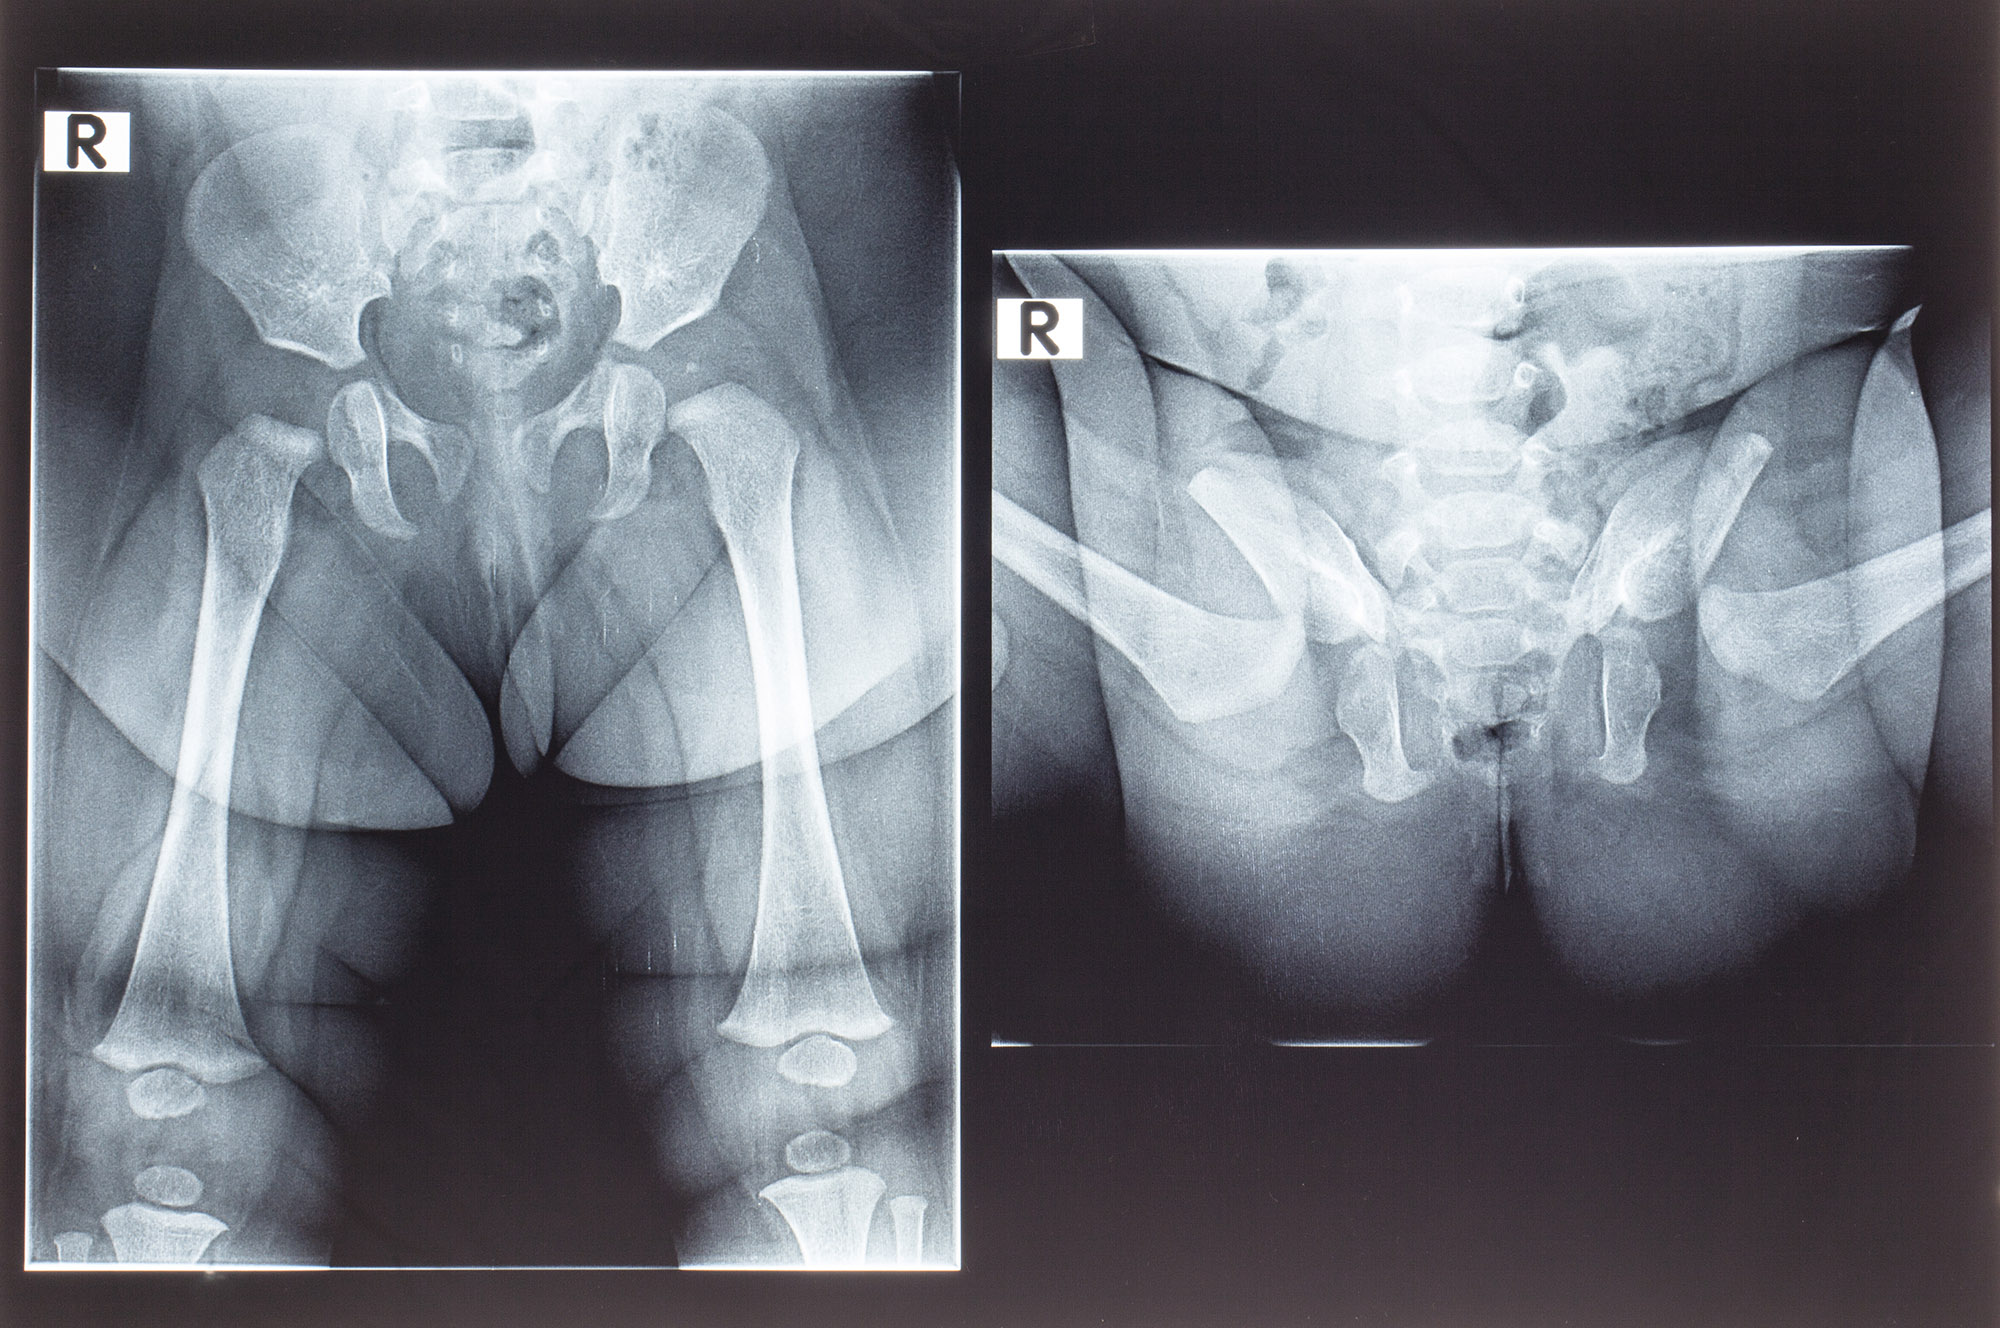

Рентген ТБС: Нормальные показатели

Раздел: Необычные решения